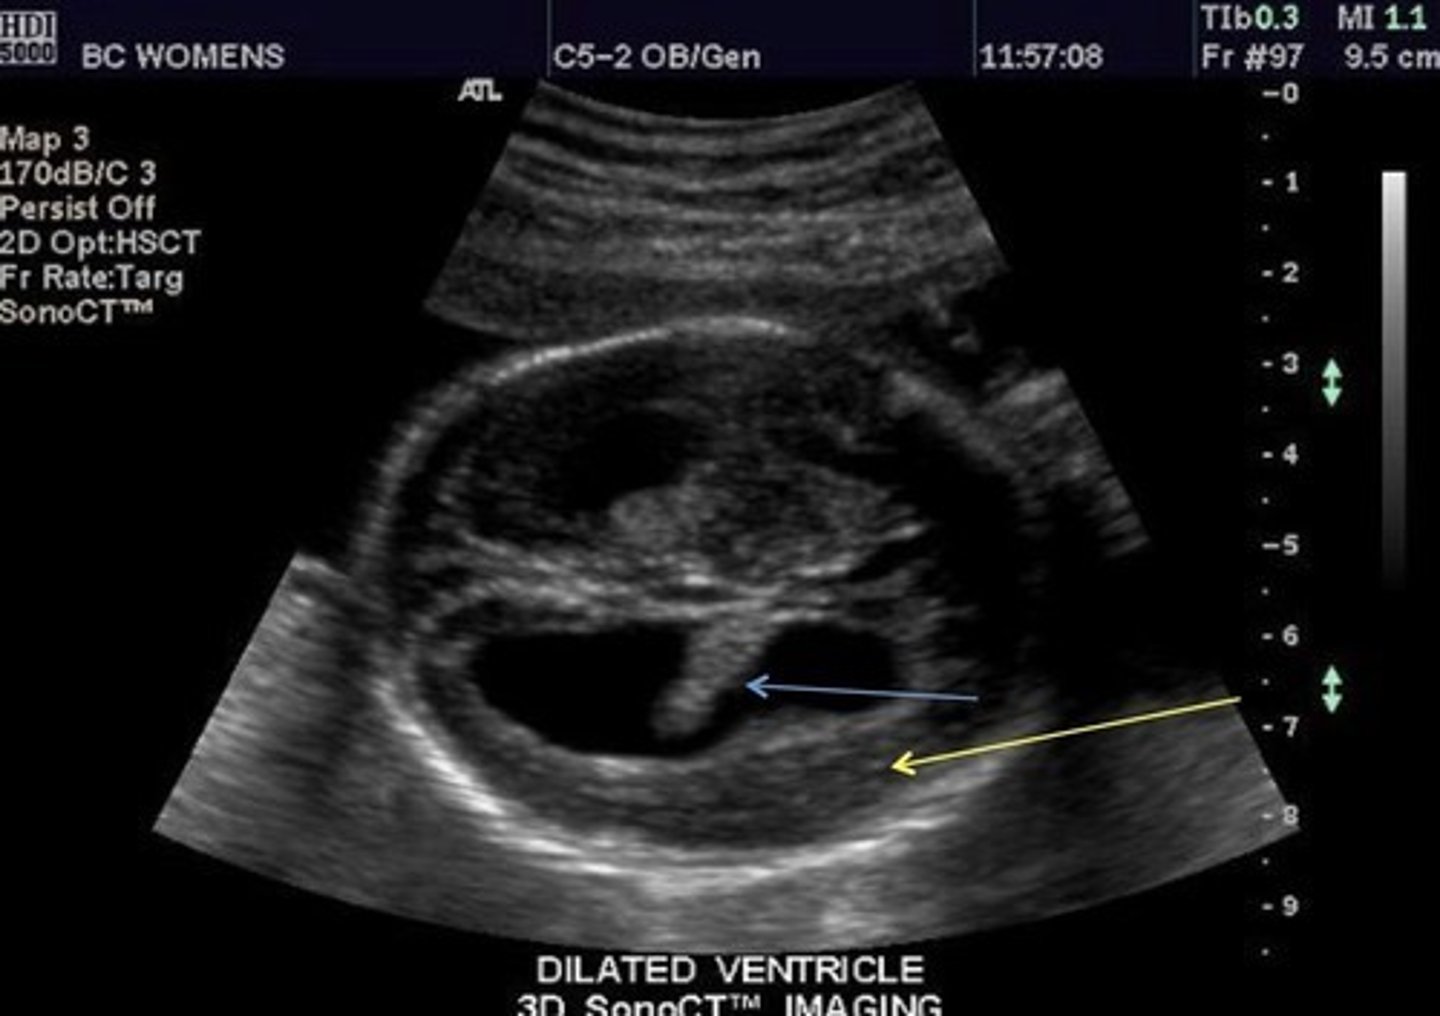

Hydrocephalus

Dilated ventricles

Dangling choroid plexus

Enlarged head